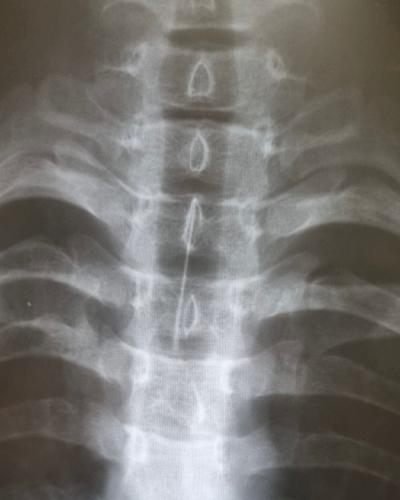

Подростка срочно повезли на рентген-исследование в больницу Ангарска, определили местонахождение опасного предмета – игла застряла в главном бронхе. Для ее извлечения мальчика экстренно привезли в Иркутск.